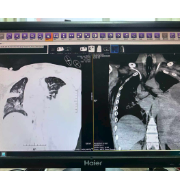

在后续CT检查中,医生发现其左肺形成了肺脓肿,并且发生了支气管胸膜瘘。“这意味着感染灶持续存在,像一个定时炸弹。”周利平教授说。为了彻底清除病灶,经过多学科团队的慎重评估,最终为他实施了左下肺叶切除术。当感染的核心被切除,这场持久战终于迎来了转折点。术后约一周,患者即出院返渝。据随访,患者复查肺部CT显示恢复良好。